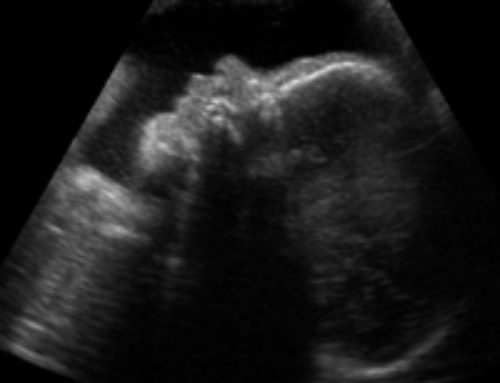

During your 3D ultrasound session we use a screening device to view the fetus during pregnancy. 3D ultrasounds are just still pictures of the fetus in three dimensions. They use high-frequency sound waves that are transmitted using a handheld probe to emit and even capture impulses produced by ultrasound waves that are emitted at different angles to come up with high resolution and clear 3D images of the baby. With the images, you can have a clear view of the umbilical cord and the placenta to access to health of the mother and baby.

3D ultrasound in early stages of pregnancy is performed by placing a transducer or a probe within the vagina or on the abdominal area where sounds waves are emitted at millions of cycles at a given second. For a bigger fetus, a transducer is moved around the mother’s belly at different angles to reveal the contours of baby features. The reflected echoes are then sent back to the computer for programming. The results are amazingly clear 3D volume images of the fetus surface and internal organs.